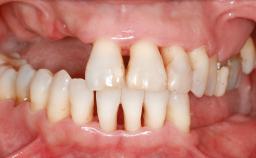

A 47-year-old woman who had suffered from aggressive periodontitis requiring a number of periodontal interventions over more than 10 years was referred by her general dental practitioner and periodontologist for bone augmentation and implant therapy. Her failing dentition had already been scheduled for extraction. The patient expressed a desire for implant-supported fixed restorations and esthetic improvement of her lower face. She had agreed to consult with a maxillofacial surgeon after the referring dentist had suggested bone augmentation. An initial examination by the maxillofacial surgeon revealed mobility of all residual teeth in a patient who was very unhappy with the function of her removable partial dentures. Due to periodontally migrated flaring teeth and loss of occlusal support, the vertical dimension of occlusion was dramatically reduced. The patient was displeased with her lower face because of deepened nasolabial, commissural, and supramental folds.